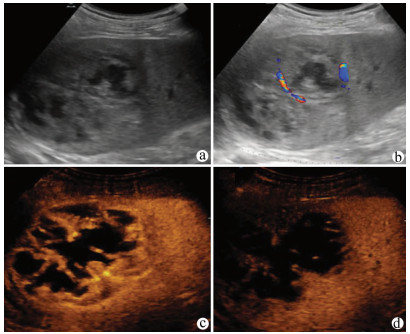

原发性肝淋巴瘤伴贫血和低蛋白血症1例报告

2021, 37(8): 1911-1913. DOI: 10.3969/j.issn.1001-5256.2021.08.034

摘要(963) HTML (226) PDF (2390KB)(53)

摘要: